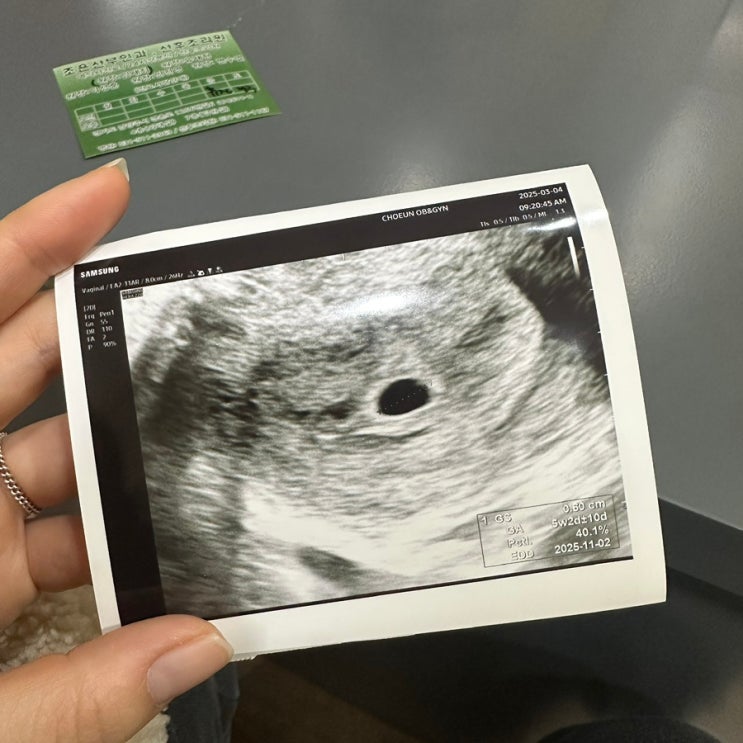

임신기록 4주차부터 8주차 기록 - 노산 비만 자연임신 입덧

기록을 남겨야지 남겨야지 해놓고 정신차리고 보니 어느덧 8주차 예비맘이 되어버렸다. 결혼 2년차로 우리...